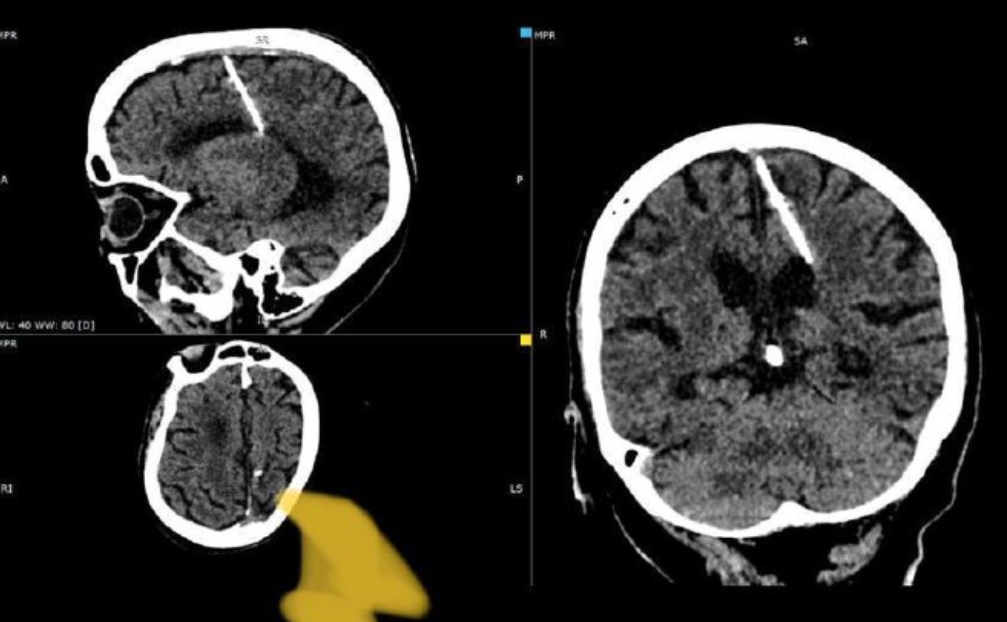

Rus doktorlar, 80 yaşındaki kadının beynine hayatı boyunca gizlenmiş bir iğneyi bularak dikkat çekici bir hayatta kalma hikayesiyle karşılaştı. İğne, beceriksizce yapılan bir bebek cinayetinin sonucu gibi görünüyor, ancak herhangi bir büyük sağlık sorununa neden olmuş gibi görünmüyor ve ortadan kaldırılmayacak.

Tuhaf vaka bu ayın başlarında Rusya’nın doğu kıyısındaki uzak bir adada keşfedildi. Sakhalin’deki yerel sağlık otoriteleri tarafından bildirildi. Doktorların, CT taraması sırasında kadının beyninde bu iğneyle ilgisi olmayan 3 santimetrelik iğneyi keşfettiği bildirildi. Sağlık Bakanlığı’ndan iğne görüntüleri Telegram sayfasında Paylaşıldı.

Şaşırtıcı bir şekilde, Kadın, parietal lobuna yerleştirilen iğneye rağmen hayatta kaldı. Üstelik yaralanma nedeniyle herhangi bir ciddi sağlık sorunu, hatta baş ağrısı bile yaşamadığı görülüyor. Ve şu anda herhangi bir tehlikede olduğu düşünülmüyor. Sağlık bakanlığından yapılan açıklamaya göre, iğneyi çıkarmaya çalışmanın kadına gerçekten zarar verebileceği ihtimali göz önünde bulundurularak, ilgili doktor kadının durumunu izlemeye karar verdi.